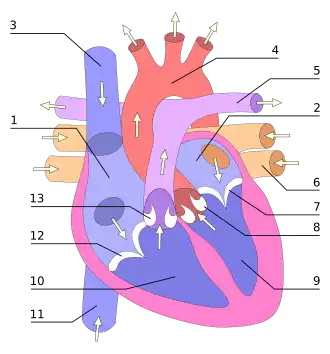

Hartklep

2. Linker atrium (boezem)

3. Bovenste holle ader

4. Aorta

5. Longslagader

6. Vier longaders

7. Mitralisklep

8. Aortaklep

9. Linkerventrikel (kamer)

10. Rechterventrikel (kamer)

11. Onderste holle ader

12. Tricuspidalisklep

13. Pulmonalisklep

Het hart bevat vier verschillende hartkleppen die verhinderen dat het bloed terugstroomt, door de bloedstroom tussen de hartboezems en de hartkamers en tussen de hartkamers en de slagaders af te sluiten. De kleppen bestaan uit materiaal van het endocard, de eerste laag van de hartwand.

De atrioventriculaire kleppen of zeilkleppen zijn de twee kleppen tussen een boezem en een kamer. Het zijn

- de tricuspidalisklep, tussen rechterboezem en rechterkamer

- de mitralisklep, tussen de linkerboezem en linkerkamer

De slagaderkleppen of halvemaanvormige kleppen zijn de twee kleppen tussen een kamer en een slagader. Het zijn:

- de pulmonalisklep of longslagaderklep, tussen de rechterkamer en de longslagader

- de aortaklep of lichaamsslagaderklep, tussen de linkerkamer en de aorta